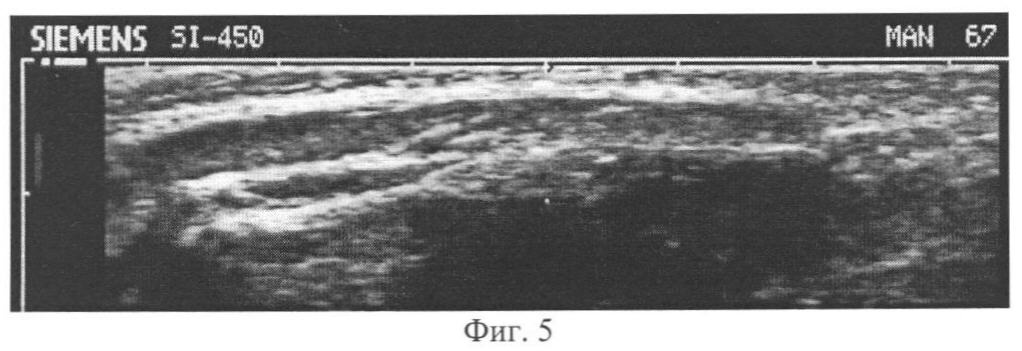

Фиг.5 – продольный УЗ-срез плечелучевой мышцы пораженного предплечья больного Л. до лечения.

Пример 2: Больной Л., 7,5 лет. Медицинская карта стационарного больного 50278, Диагноз: врожденная аномалия развития левой верхней конечности. Локтевая косорукость. Гипоплазия левой верхней конечности. Трехпалая кисть. Синдактилия II-III пальцев. УЗИ плечелучевой мышцы (m. brachioradialis) пораженного предплечья в исходном состоянии – до оперативного лечения, в процессе воздействия деформационной нагрузки – дистракционном периоде, в периоде релаксации (фиксации), в восстановительном периоде после снятия аппарата.

Пациент находился в горизонтальном положении, лежа на спине. Линейный датчик устанавливали в средней трети пораженного предплечья продольно параллельно продольной оси конечности – в проекции брюшка плечелучевой мышцы. Осуществляли сонографию плечелучевой мышцы, получали ее поперечные и продольные УЗ-срезы, в режиме on line проводили компьютерную обработку полученных сонограмм с определением моды гистограммы распределений эхоплотности выделенной курсором области мышцы.

(1) OCCHM m. brachioradialis=(39-31)/39=0,21;

(2) OCCHM m. brachioradialis=(22-20)/22=0,09;

(3) OCCHM m. brachioradialis=(41-36)/41=0,12;

(4) OCCHM m. brachioradialis=(29-19)/29=0,34.

Характеристики OCCHM плечелучевой мышцы пораженного предплечья в исходном состоянии соответствуют умеренно пониженной сонографически структурной неоднородности плечелучевой мышцы, в процессе дистракции – низкой, в стадии релаксации – умеренно пониженной, в восстановительном периоде – физиологически нормальной структурной неоднородности плечелучевой мышцы.